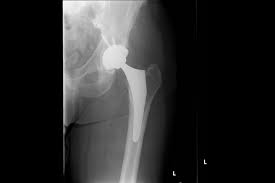

Hip replacement surgery can be performed as a total replacement or a hemi (half) replacement. In a hip resurfacing surgery, the implant is smaller, and less normal bone is removed. Learn what to expect when preparing & undergoing surgery. Albright discusses alternatives to hip replacement surgery. This involves removing the damaged surfaces of the bones inside the hip joint and replacing them with a metal surface.

Hip revision (a repeat hip replacement) surgery involves replacing your artificial hip joint if it's become loose, infected or worn out. Hip replacement surgery can be performed as a total replacement or a hemi (half) replacement. Alternatives to hip replacement surgery include conservative management, hip resurfacing, hemiarthroplasty, and viscosupplementation. Hip replacement surgery involves replacing the hip joint with new artificial joint parts. Hip replacement surgery and hip resurfacing are often the only surgical options presented to a patient to deal with their debilitating pain, though hip the innovative regenexx procedures restore hip function and mobility and decrease pain without the need for surgery by regenerating damaged. Direct anterior total hip replacement surgical procedure video. The most common conservative alternatives to hip replacement surgery are assistive devices (canes or walkers) to reduce stress on the affected hip there are both surgical and nonsurgical options to treat a herniated disc. Statistics and hip replacement therapy. Surgery and increase hip function. Some joint preservation procedures are newer and considered experimental, dr. A hip replacement procedure is a major surgical operation that is usually only reserved for cases where alternative therapies have failed. Hip replacement surgery is one of the most successful modern orthopedic surgical procedures. Lifestyle and medical options can help reduce discomfort and slow the damage.

Learn about hip replacement surgery, total hip replacement and partial hip replacement. Before opting for knee replacement surgery, it's important to consider all your options. Last updated may 24, 2019by howard j. Nonsurgical treatments include medication and going to a chiropractor. There is an alternative type of surgery to hip replacement, known as hip resurfacing. Hip replacement surgery can be performed as a total replacement or a hemi (half) replacement. Have you considered all the hip replacement alternatives available? Knee assessment and hip mechanics online course: Hip replacement surgery involves replacing the hip joint with new artificial joint parts. Some examples of the alternative approaches to treating damaged or painful hips are described below. Hip replacement is a surgical procedure in which the hip joint is replaced by a prosthetic implant, that is, a hip prosthesis. How long you stay in the hospital or surgical center after your surgery depends on many factors, including your overall health. Hip replacement surgery removes damaged of a hip joint & replaces them with new parts.